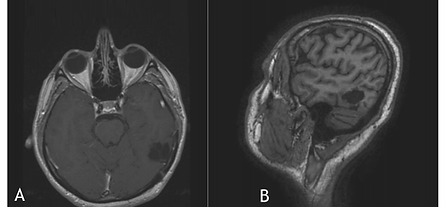

Ameliyat sonrası dönem sorunsuz geçti. Hastanın erken ve geç dönem MR görüntülerinde tümörün tekrarlamadığı gözlendi. Ameliyattan 3,5 yıl sonraki takipte, hastanın hiçbir şikayeti kalmamıştı ve radyolojik olarak da tümörün tekrarlamadığı görüldü.

Ameliyattan bir gün sonra çekilen MR görüntülerinde tümörün tamamen çıkarıldığı görülüyor.

Ameliyattan yaklaşık 3,5 yıl sonraki MR görüntülerinde tümörün nüks etmediği (tekrar oluşmadığı) gözleniyor.